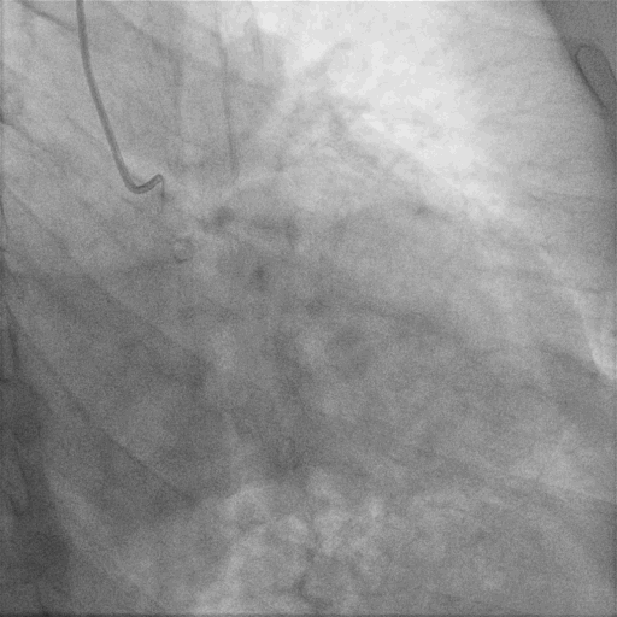

左图:LM未见狭窄及阻塞病变;

右图:LCX未见狭窄及阻塞病变;

左图:LAD近段可见斑块,中段原支架通畅,未见狭窄及阻塞病变;

右图:RCA开口狭窄约50%,近段中段弥漫性斑块,远段后侧支第二转折处局限性狭窄90%;

患者不稳定型心绞痛症状典型,根据心电图及冠状动脉造影术结果回报,考虑罪犯血管为右冠脉远段后侧支第二转折处病变;

右冠状动脉全程迂曲伴钙化,可能会为随后器械推送带来阻力和困难;